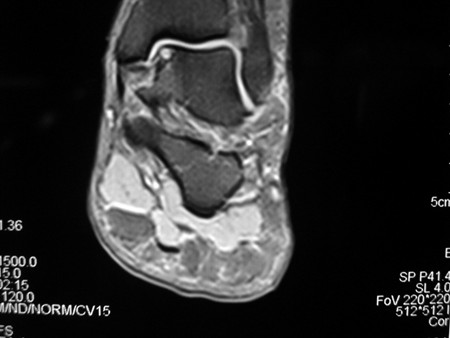

Coronal MRI image of the talus, showing an osteochondral lesion on the medial aspect of the talar dome

Gupta RK, Kansay R, Aggarwal V, et al. Osteochondritis dessicans of the talus in a 26-year-old woman. BMJ Case Reports 2009; doi:10.1136/bcr.06.2008.0091